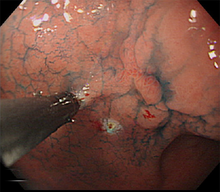

胃がんは、胃の壁の最も内側にある粘膜内の細胞が、何らかの原因でがん細胞になって無秩序に増殖を繰り返すことで生じます。胃がん検診などの検査で見つけられる大きさになるまでには、通常何年もかかるといわれています。胃がんの診断には胃の内側から内視鏡(胃カメラ)で観察することにより診断が可能であり、胃がんの部分がイボのように盛り上がったり、潰瘍を形成し陥凹している部分、色調の変化した部分などを詳しく観察します。生検検査でがん細胞を認めると診断が確定します。胃がんの内視鏡写真を提示します(図1)。

がん細胞の増殖の仕方によって「分化型胃がん」と「未分化型胃がん」に分かれます(図2)。分化型胃がんでは、もとの正常な細胞の特徴を残したまま塊を作って大きくなります。一方、未分化型胃がんは、もとの細胞の構造がほとんど見られずバラバラに広がり、がんの範囲も分かりにくいです。とくに未分化型胃がんのなかで、粘膜に発生した癌が表面を広がらないで粘膜の深いところを這うように広がって行くタイプ(スキルス胃がん)では診断がつきにくく、かなり進行しないと見つかりにくい場合もあります。